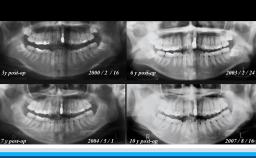

超高齢社会への移行に伴って、有病者へのインプラント治療が多くなってきている。本レクチャーでは代表的な疾患な疾患を有する患者のインプラント成功率が紹介されるとともに、インプラント治療時の注意が示されている。

• 糖尿病患者、高血圧症患者に対するインプラント治療法

• 抗凝固剤服用患者に対するインプラント治療法

• 放射線照射患者に対するインプラント治療法